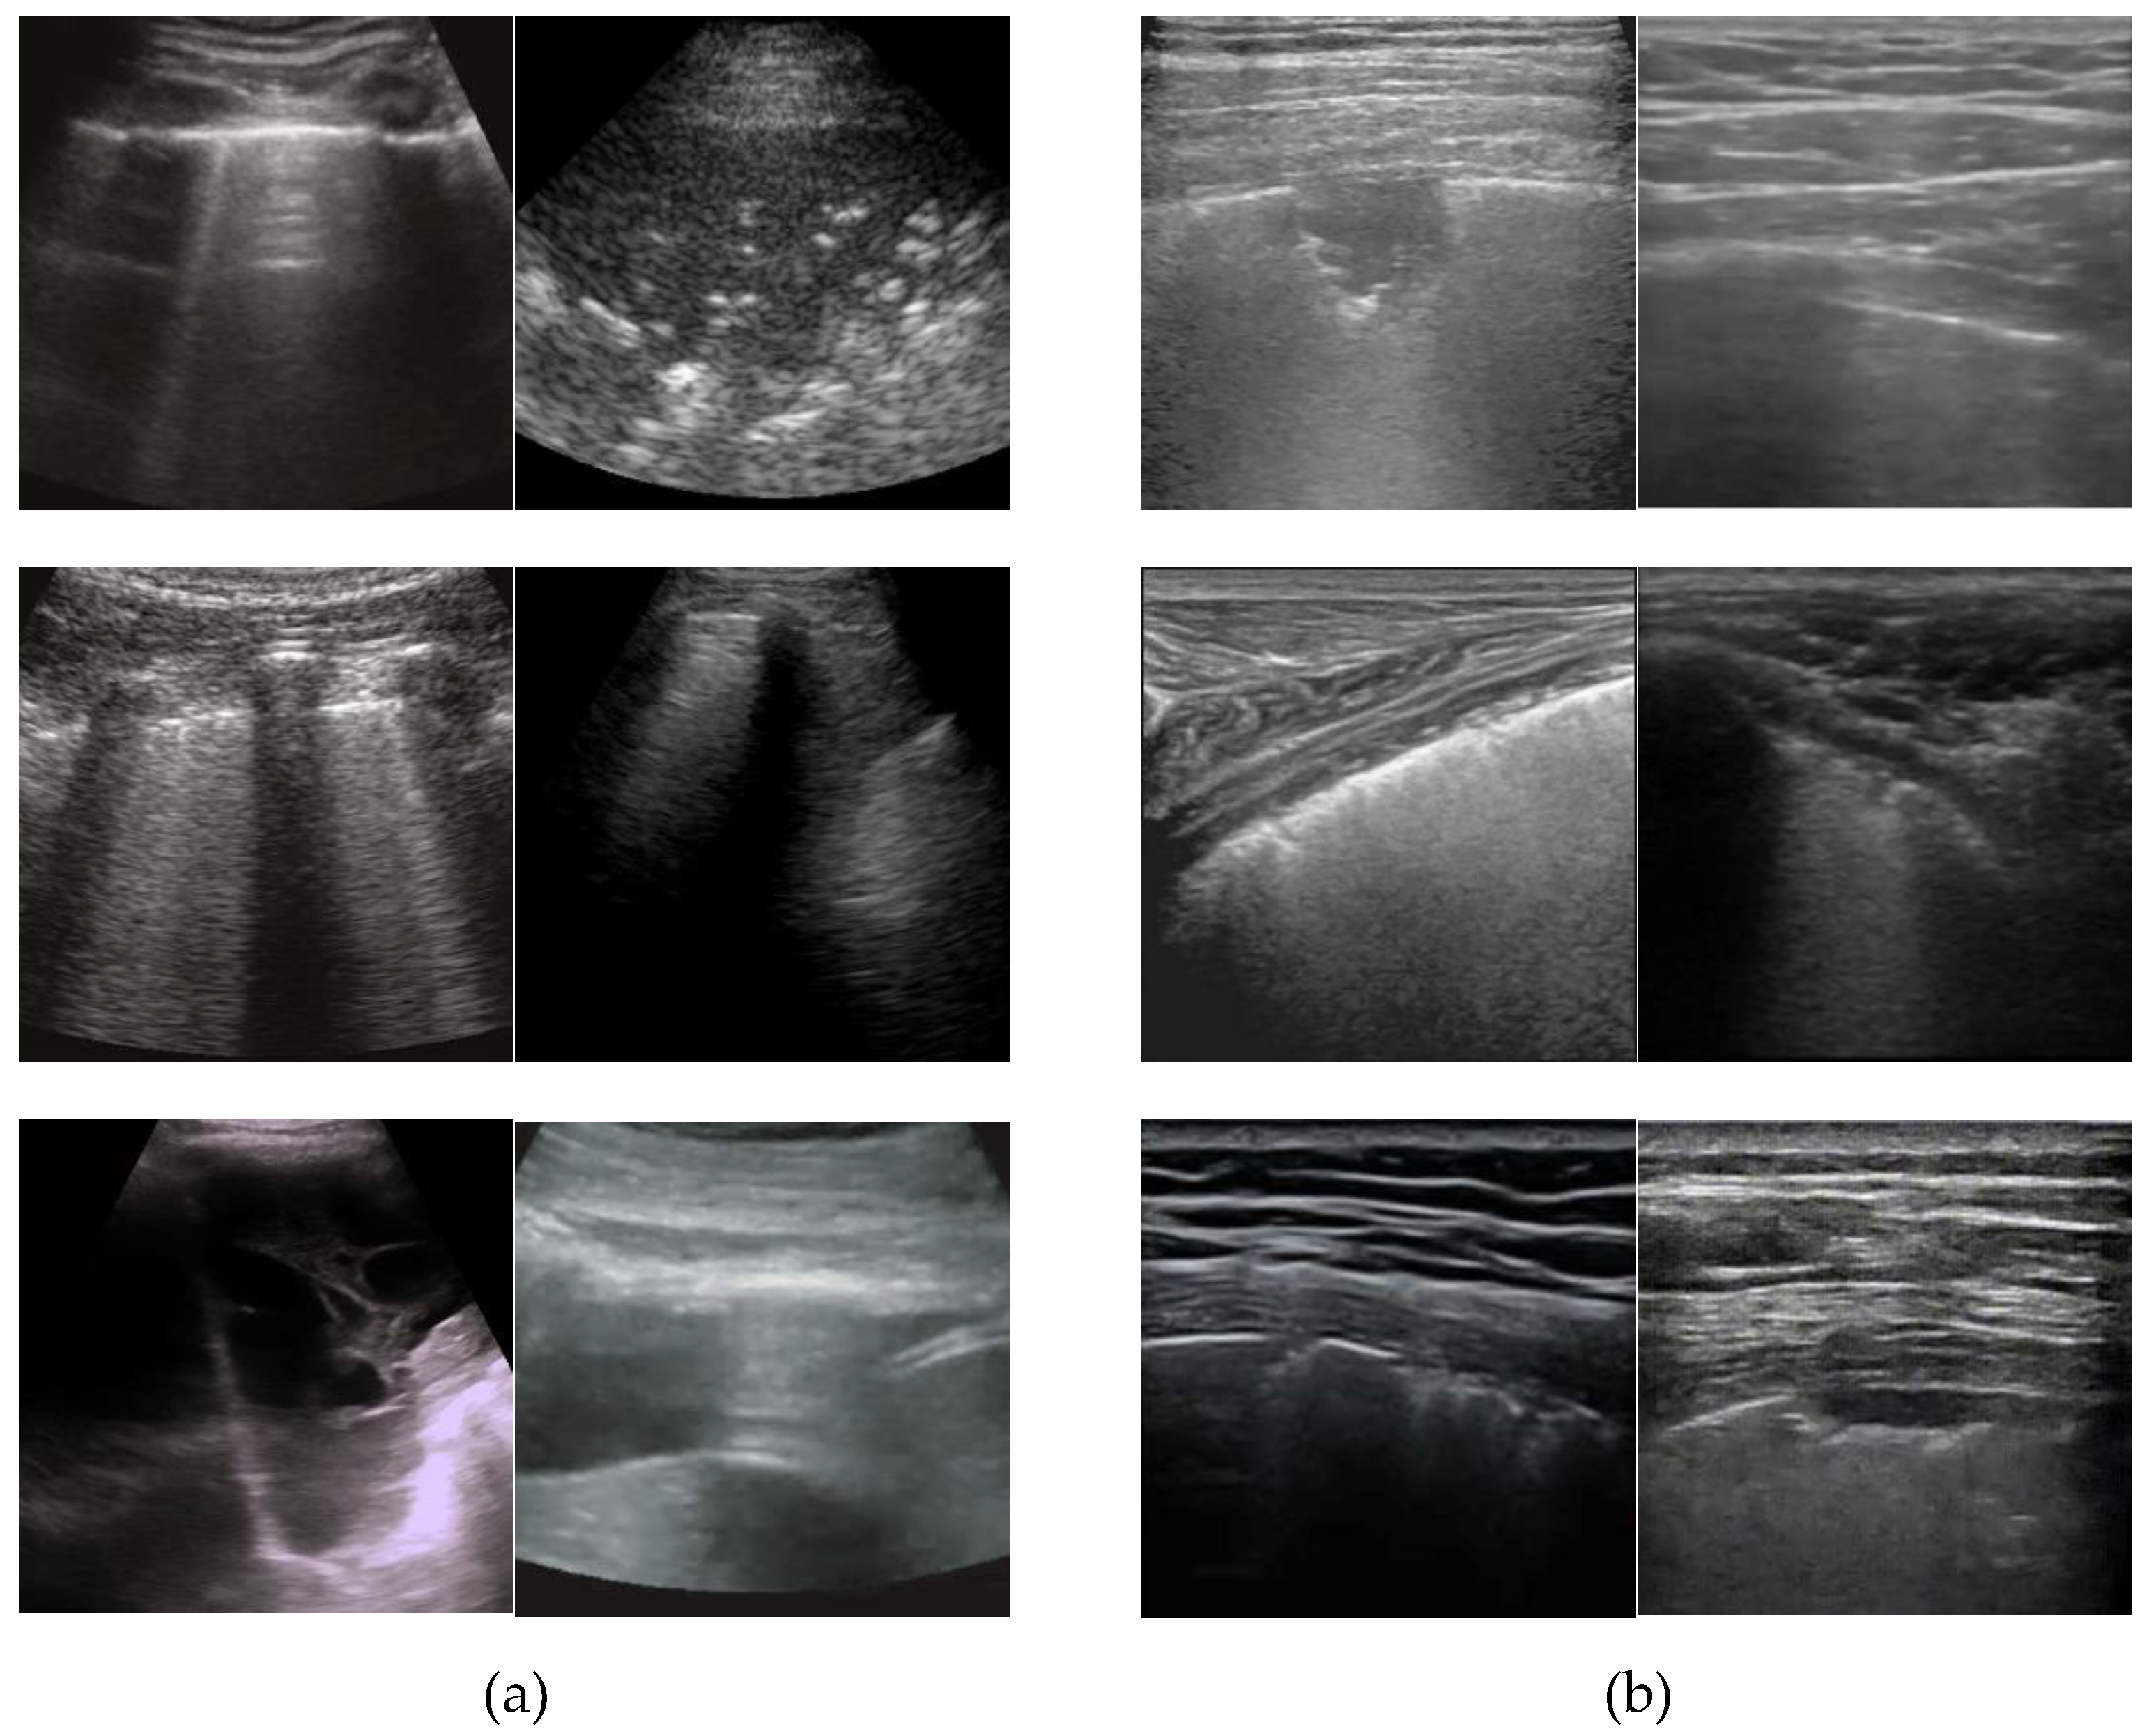

Figure 1 shows examples of ultrasound images obtained from different probes and records, where the left two columns (a) represent images from several records captured using convex sensor, and the right two columns (b) represent images from different records captured using a linear sensor.

Figure 1. Examples of ultrasound images obtained from different probes and records using (a) a convex sensor and (b) a linear sensor.